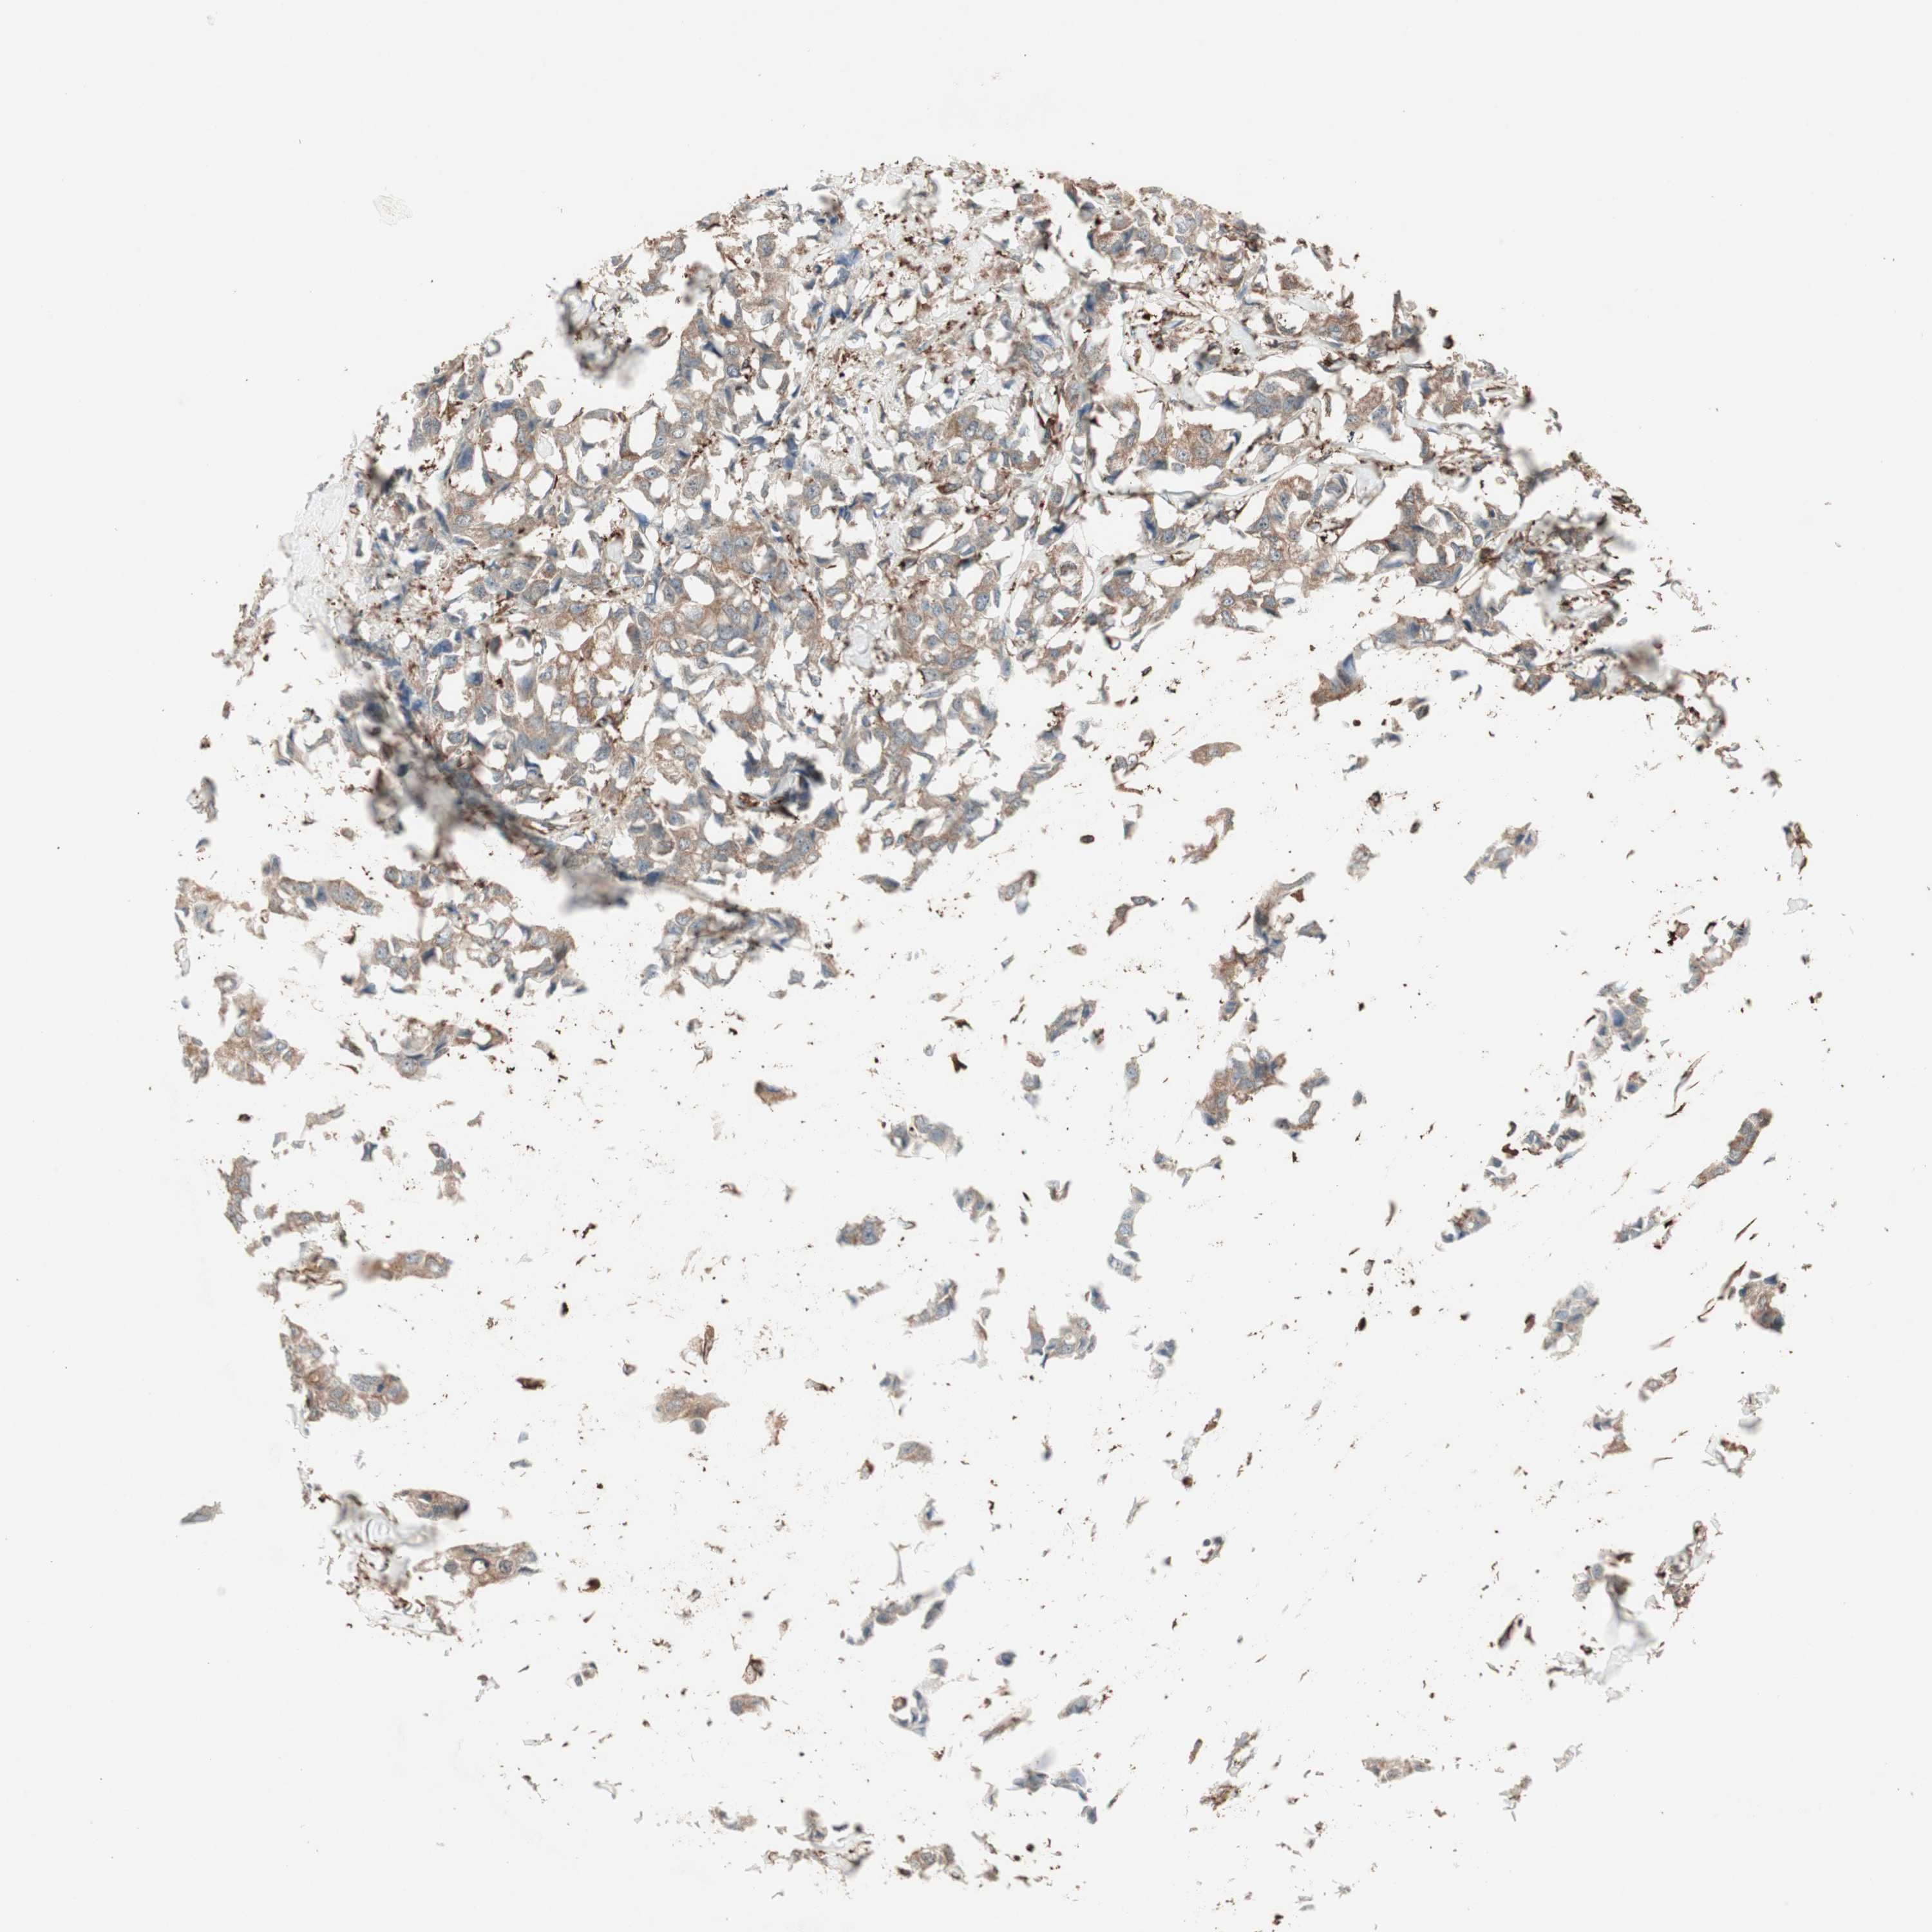

BRCA TCGA BRCA VALIDATION PROTEIN EXPRESSION